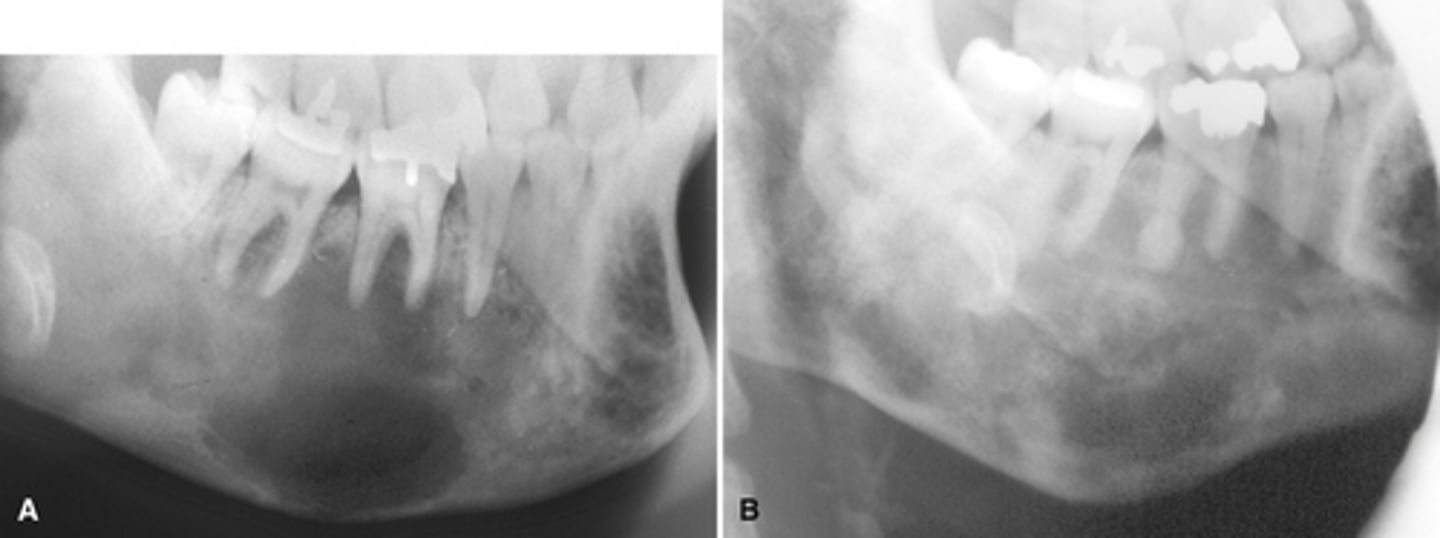

RA (rheumatoid arthritis)

Image A shows a lateral ceph where the patient has a steep mandibular plane and anterior open bite.

Image B shows erosion of the temporal component of the TMJ

What is the diagnosis of the patient based off these radiographs and what are the features?